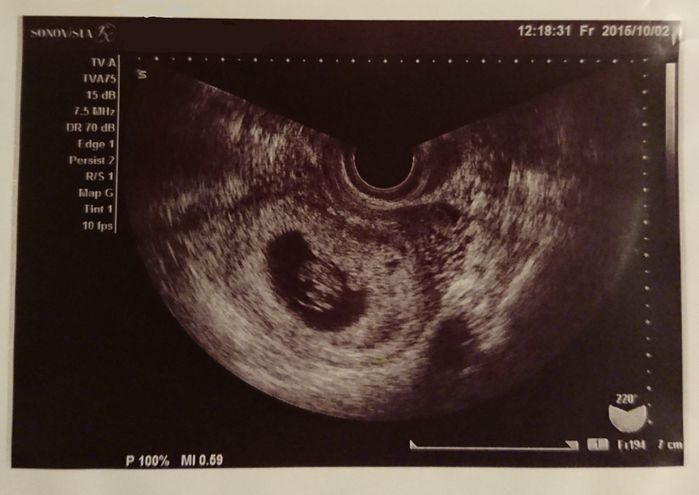

妊娠5週目 胎嚢を確認!

妊娠検査薬で陽性反応が出てから1週間後、産婦人科を受診し、初めてのエコーで胎嚢を確認しました。この時すでにつわりが始まっていたので常にムカムカしている状態です。